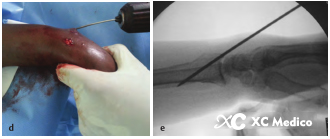

Во -первых, выполняется закрытое восстановление перелома, с медленной и непрерывной тягой, а дорсальное и радиальное смещение корректируется с помощью сгибания пальма и локтевого отклонения. После сокращения рука помещается на свернутый лист, поддерживая пальмовое сгибание и локтевое отклонение (рис. 2а, б) и фиксируется не менее трех чрескожных проводов Киршнера.

Первый K-провод вводится в бугорку Листера, наклонен при 45 ° и направлена на пальмовую кору проксимального фрагмента кости на длинной оси радиуса. Если точка вставки находится на локтевой стороне бугорки Листера, сухожилие Extensor Ollicis может быть повреждено.

Вторая K-провода вставлена 0,5 см дистальна к радиальному стилоидному процессу, K-провода находится под углом 60 ° к радиальной оси и проникает в локтевую кору, проксимальную к перелому.

Третий K-провода фиксируется к фрагменту Lunate Fossa Bone 0,5 см дистально до линии сустава запястья, расположенной между четвертым и пятым компартментами разгибателей. K-провода прикреплена к ладонильной стороне радиуса под углом 45 °, как показано на рисунках A и B ниже.

Классическая чрескожная фиксация проволоки Киршнера расстановки дистального радиуса показана на рисунках AE ниже.